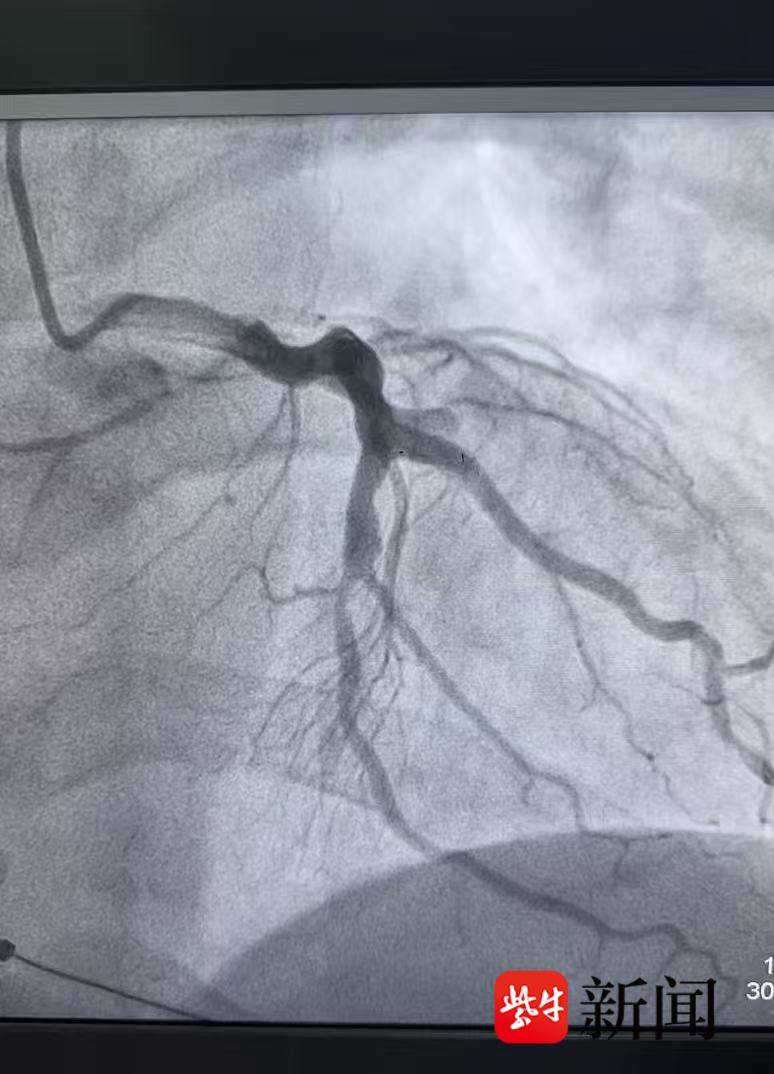

患者被紧急转运至苏州市吴中人民医院后,立即接受急诊冠状动脉造影检查,明确为急性心肌梗死相关血管闭塞。吴中人民医院孙中奇医师迅速为患者实施急诊介入治疗,成功开通闭塞血管,患者术后恢复良好。经过规范治疗与监护,患者病情稳定,已于12月16日顺利出院。

血管开通前

血管开通后